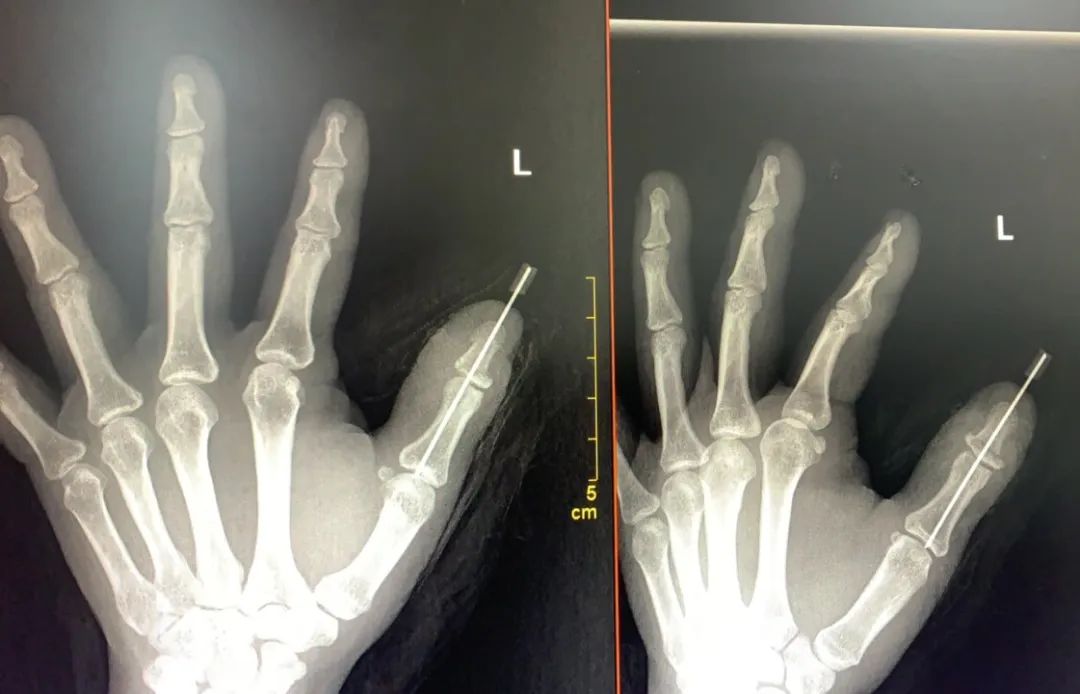

经过充分的术前准备后,手足外科团队聚精会神、沉着冷静,在显微镜下,有条不紊将断裂的血管、神经、肌腱等一一吻合,每一步都小心翼翼,稍有不慎就会影响断指的成功率。经过近两小时的手术,跨越一道又一道难关,患者的血管终于实现吻合,血管通常,毛细血管反应灵敏,手术非常成功。

目前患者再植指成活良好,伤口基本愈合,待手指进一步稳定后,再逐步指导其行功能训练等后续康复方面的处理。